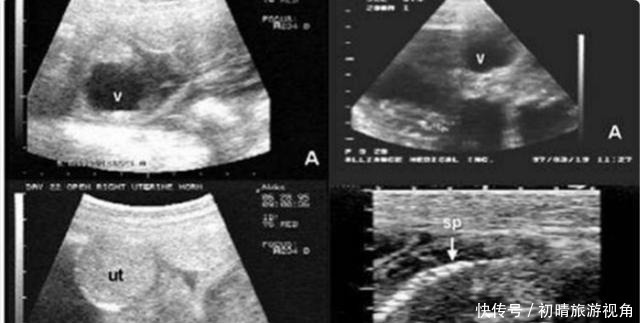

这对英国的夫妻,在结婚多年后才拥有了自己的孩子,妻子在怀孕的时候就非常的喜悦。他们如期进行孕检,却没想到在怀孕三个月的时候去医院检查被医生告知胎儿的脊柱存在断裂的情况,希望这对夫妻放弃这个孩子,可是这对夫妻并没有放弃。在怀孕8个月的时候去产检,医生告诉他们,胎儿目前这个情况,即使是出生,孩子大脑发育也不完全,抚养困难很大。

孩子生下后,经过诊断,正如医生所说的那样大脑发育只有平常人的百分之二,很难存活。即使这样,这对夫妻还是没有放弃孩子,三年了他们到处求医给孩子治疗,用心陪伴,直到今天,孩子大脑的发育已经到百分之八十了,会简单的语言,父母也因此而感到欣慰,不得不说这还真是一个奇迹。

胎儿脊柱裂有什么影响?胎儿脊柱裂是一种先天性的骨骼疾病,可以在孕18-22周检查出来。其包括两种情况,一种是隐性的,另一种是显性的,显性脊柱裂会影响到宝宝以后的下肢活动,大小便失禁,甚至会影响智商,隐性脊柱裂一般不会有太大影响。如果查出胎儿是显性的脊柱裂,一般情况下医生都会建议终止妊娠。